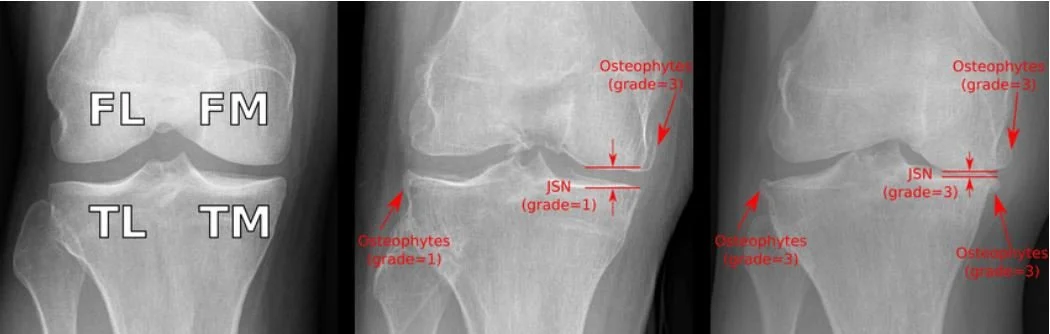

2. JSN Grades